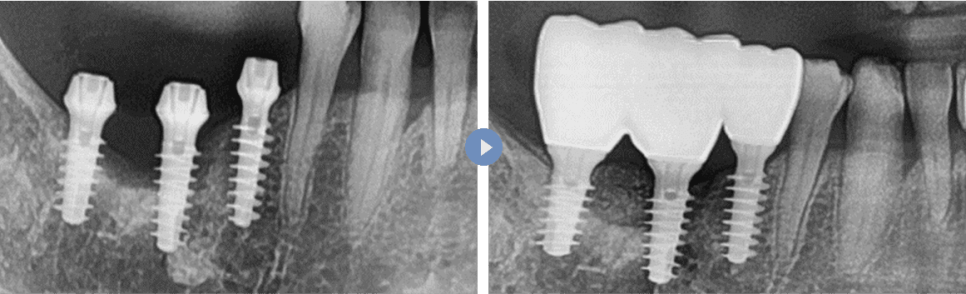

뼈이식 수술(비노출형)

뼈이식 전 CT 단면 > 비노출형 뼈이식 후 CT 단면 > 뼈이식 최종 완성 후 CT 단면

잇몸뼈의 외부 높이와 넓이를

증강하는 뼈이식 수술

뼈이식 전 무절개 임플란트 식립만 한 단계 > 뼈이식 완성 후 최종 보철 후 단계

무절개 임플란트 뼈이식 수술 후

최종 보철물이 안정적으로 자리 잡는

결과를 보여줍니다.